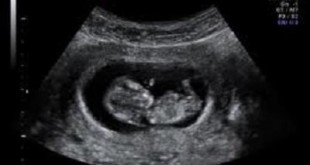

- Giúp theo dõi sự phát triển của một thai nhi và kiểm tra các bất thường. Siêu âm định kỳ cho phụ nữ mang thai.